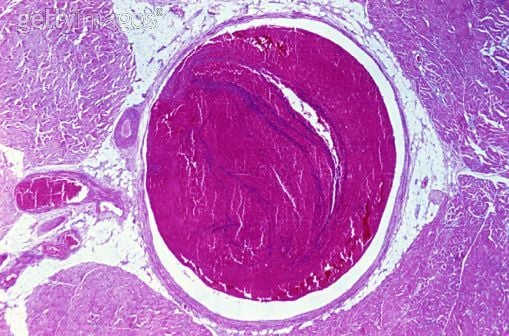

Normális esetben az érpályán belül áramló vér folyékony halmazállapotú. Kóros körülmények közt a vér az érpályán belül, rendszerint valamelyik vénában megalvadhat. Az érpályán belüli véralvadás esetén a keringő vérben vérrög alakul ki. A vérrög elzárja a vérkeringést. Érelzáródás esetén az adott ér által ellátott területek vérellátása károsodik. A vérkeringési akadály miatt az adott terület szövetei nem kapnak elegendő vért és oxigént. Az oxigénhiány szövetkárosodáshoz, szövetelhaláshoz vezet.Ha az érpálya valamelyik szakaszán kialakult vérrög a vérkeringés során elvándorol a keletkezés helyéről, a vérárammal tovasodródik, majd valahol egy szűkebb érszakaszán megakad és elzárja a vér útját, embólia jön létre. Az embólia súlyos, halálos kimenetelű szövődményeket okozhat.Agyi vénás trombózis esetén valamelyik agyi vénában kóros véralvadás és vérrögképződés jön létre. A vérrög elzárja az agyi vénát.A vérrögösödés az agyhártyák közt található vénás tágulatokban, tág agyi vénás öblökben a leggyakoribb.Agytrombózis esetén a keringés akadályozott, a koponyán belüli nyomás növekszik. A nyomásfokozódás fejfájást, tudatzavart, idegrendszeri zavarokat, perifériás bénulásokat, eszméletvesztést okoz. Az agy szövetállománya károsodik, az agyvérzéses tünetekhez hasonló maradandó károsodások lépnek fel. Súlyos esetben az agytrombózis halálos kimenetelű.A vérzés-alvadás egyensúlyának felbomlása esetén az érpályán belüli véralvadás veszélye növekszik.A nagymérvű sérülések, a nagyobb műtéti beavatkozások megbonthatják a kényes egyensúlyt, a véralvadási készség fokozódhat.A fogamzásgátló tabletta és a terhesség szintén fokozza a vér alvadékonyságát.A fej területén kialakuló gyulladásos folyamatok, melléküreg-gyulladások esetén agyi vénás trombózis alakulhat ki. Az agyi vénás gyulladás szintén agyi vérrögösödést okozhat.Az érelzáródást okozó vérrögöt hat órán belül fel kell oldani. A vérrög intravénásan adott, enzimhatású gyógyszerrel oldható.Ha a vérrög feloldására nincs lehetőség, az ép agyi területek vérellátását értágító infúziós kezeléssel javítják.Bizonyos esetekben a vérrög műtéti eltávolítása válik szükségessé.Görcsroham, bénulás, zavartság, eszméletvesztés esetén azonnal hívjunk mentőt.Az agyi vérkeringés fokozatosan romlik.A betegség kezdetén fejfájás, szédülés, hányinger jelentkezik. Az agykárosodás miatt perifériás, az egyes izomcsoportokra illetve a teljes testre kiterjedő izomgörcsök alakulnak ki. A beteg tudatállapota egyre jobban beszűkül, zavarttá válik, majd eszméletét veszíti. Az eszméletlen beteg a külső ingerekre nem reagál.Az agytrombózis következtében egyes perifériás izomcsoportoknak maradandó bénulása alakulhat ki.Kezeletlen agyi trombózis esetén halálos kimenetelű agynyomás-fokozódás léphet fel.